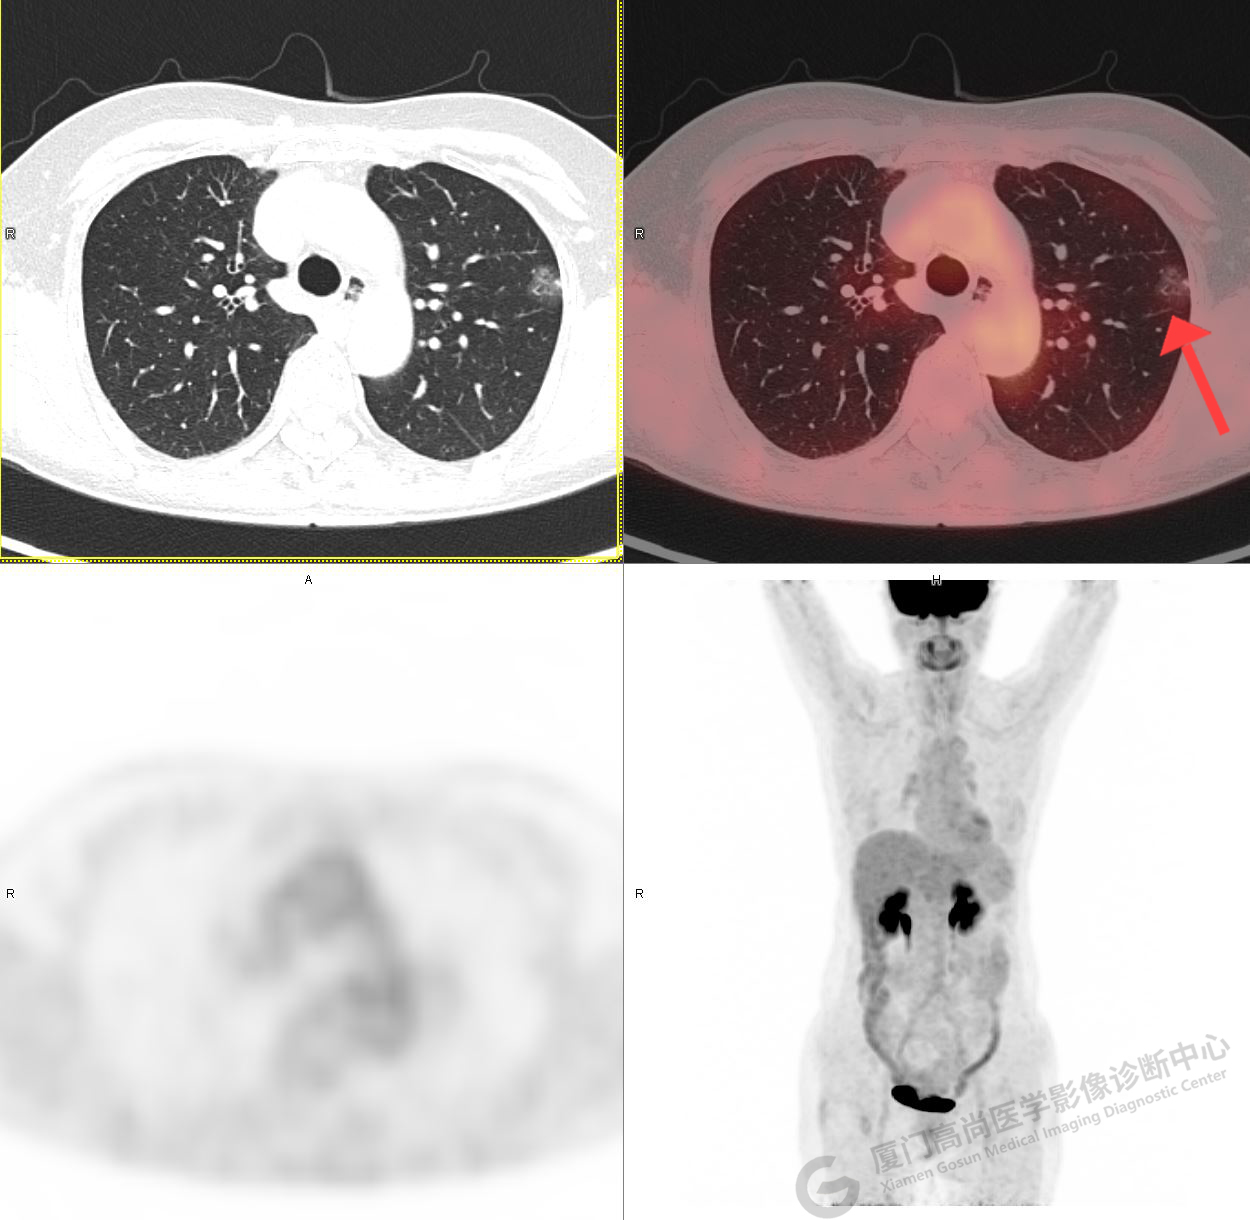

PET/CT影像圖

圖1

圖2

PET/CT示:1、左肺上葉混雜磨玻璃結(jié)節(jié),代謝不高,考慮為浸潤性腺癌,建議病理學(xué)檢查。2、右肺中葉混雜磨玻璃結(jié)節(jié),代謝不高,考慮為腫瘤性病變(微浸潤性腺癌?),建議密切CT復(fù)查。3、右肺上下葉純磨玻璃結(jié)節(jié),代謝不高,雙肺下葉少許結(jié)片影,代謝不高,考慮為炎癥。